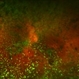

- Left fundus photograph of a 50-year-old female patient with spontaneous retinal reattachment five years after visual loss.